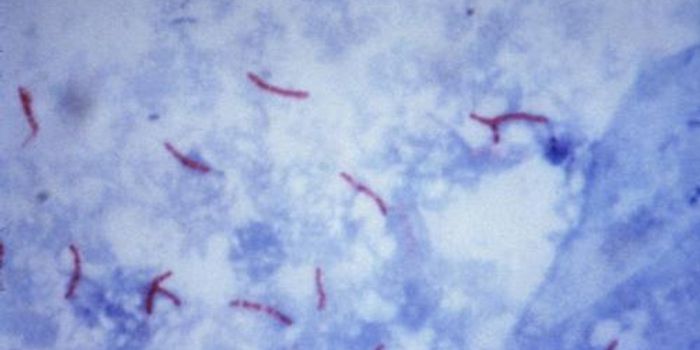

MAR 31, 2015Genetics & GenomicsResearchers have identified blood-based biomarkers in patients with active tuberculosis (ATB) that could lead to new blo ...